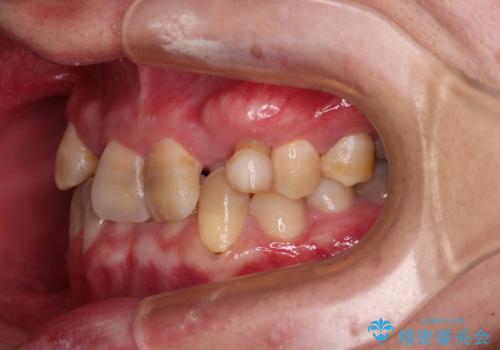

- 上下の前歯のデコボコを改善したいと来院された患者様です。

上顎の歯列幅が狭く、それによって歯が並ぶスペースが不足しています。

また下顎の歯列幅も制限され、内側に歯が倒れています。